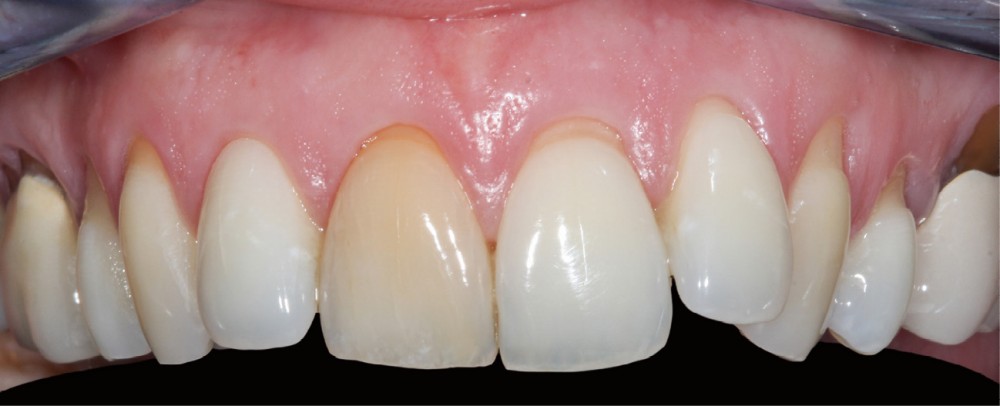

L’éclaircissement dentaire peut être réalisé à domicile (technique ambulatoire) à l’aide de gouttières porte-gel sur mesure fabriquées après prise d’empreinte (fig. 1), ou au cabinet par application de gel après isolation et protection des tissus mous (fig. 2).